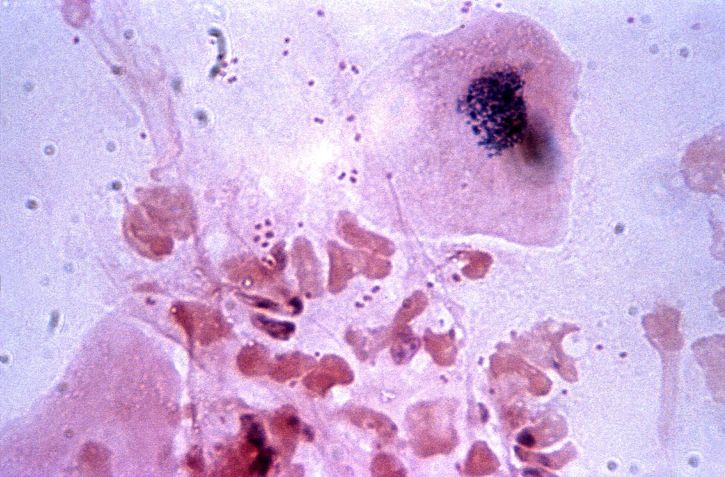

백혈구는 혈액 속에 존재하는 세포 중 약 1% 이하의 비율을 차지하며, 면역 기능을 수행하여 바이러스와 세균과 같은 외부 물질로부터 우리 몸을 방어하는 역할을 합니다. 백혈구는 총 5개의 종류로 나뉘며, 림프구, 호중구, 호산구, 단구, 호염기구로 구성됩니다. 백혈구의 정상 수치는 성인을 기준으로 5000~10000 정도입니다.

백혈구 수치가 낮아지는 원인은 다양합니다. 인체면역결핍바이러스, 골수 질환, 비장 및 간 질환, 호중구 감소증, 자가면역질환 등이 있을 수 있습니다. 또한 백혈구 수치 낮아지면서 세균, 곰팡이, 미생물로 인한 감염 위험이 증가할 수 있습니다.